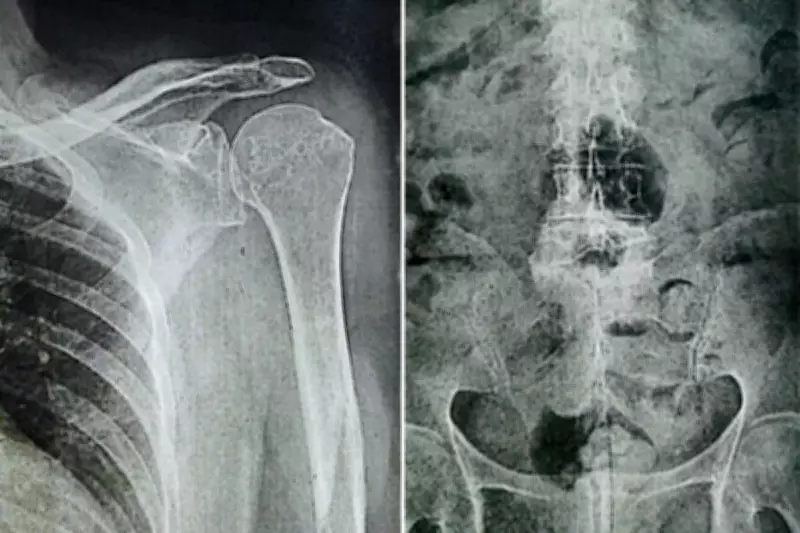

A idosa sofreu lesões significativas no ombro, na coluna e na cabeça, necessitando posteriormente do auxílio de terceiros para realizar atividades básicas do dia a dia. Os profissionais jurídicos inicialmente pediram uma indenização equivalente a pelo menos 50 salários mínimos, valor que foi ajustado para R$ 20 mil pelo juiz Frederico dos Santos Messias, da 4ª Vara Cível de Santos, em julho de 2025.